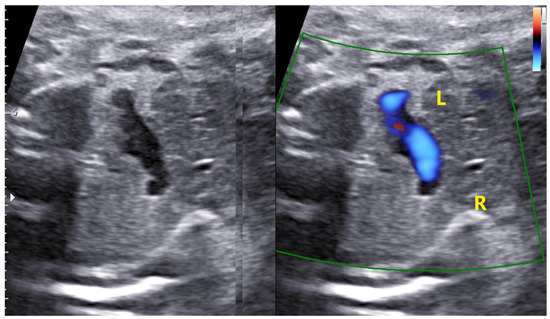

4.4. Case 4